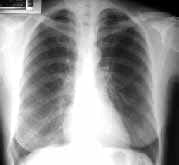

La TAC con cortes de alta resolución, mostró imágenes quísticas parenquimatosas multilobares, con diámetros entre 2 y 5 mm, la mayoría de las cuales, presentaban pared fina ( Figura 2). La revisión de la biopsia pulmonar se interpretó como linfangioleiomiomatosis ( Figuras 3 y 4).

| Figura 1. Radiografía PA de tórax. Opacidades reticulares finas. Figura | Figura 2. TAC de alta resolución. Lesiones quísticas, de pared fina, comprometiendo el parénquima pulmonar en forma difusa. |

En la TAC de alta resolución, el hallazgo más frecuente es la presencia de quistes, de tamaño variable (2 mm-5 cm), de pared fina, rodeados por parénquima pulmonar relativamente normal, que se visualizan en el 100% de pacientes con linfangioleiomiomatosis.

En ocasiones los quistes no presentan pared definida y su morfología es irregular, lo que dificulta el diagnóstico. La distribución de los quistes es difusa, sin predilección por ninguna zona del pulmón y aumenta con la progresión de la enfermedad.

Hay una buena correlación entre las pruebas funcionales, las manifestaciones clínicas y la profusión de los quistes (2, 7, 8). Se han informado otras manifestaciones torácicas como: derrame pericárdico, dilatación del conducto torácico y adenomegalias mediastinales (2, 7).